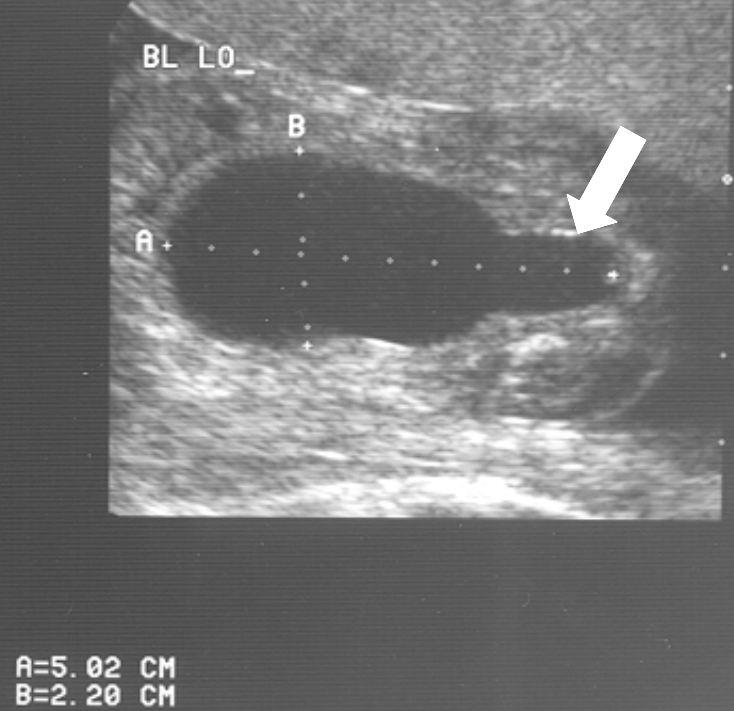

Normale plasbuis voorbij de kleppen

Plaats van de urethrakleppen

Verwijd eerste deel van de plasbuis tot aan de kleppen

Kleine, kramperige blaas met kartelige contour veroorzaakt door uitstulpingen van de blaaswand (divertikels)

Terugstroom van urine tot in de nier (vesico-ureterale reflux) en verwijde urineleider

Plasfoto met contrastmiddel (mictie cystogram)